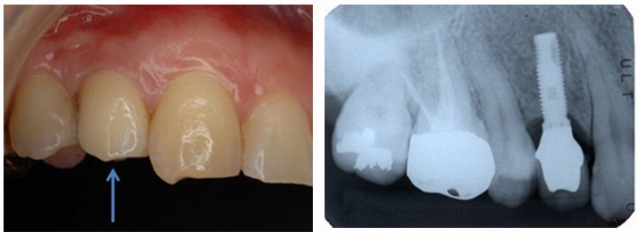

最終的に装着された歯と術後のレントゲン写真

インプラント治療後、定期的にメインテナンスをおこなっていた患者さんであっても、10年後には28.6%がインプラント周囲炎(炎症でインプラント周囲の骨がなくなる状況)を発症したというデータもあります。治療後は必ずインプラントの部位はもちろん、口腔全体をメインテナンスしていく必要があります。